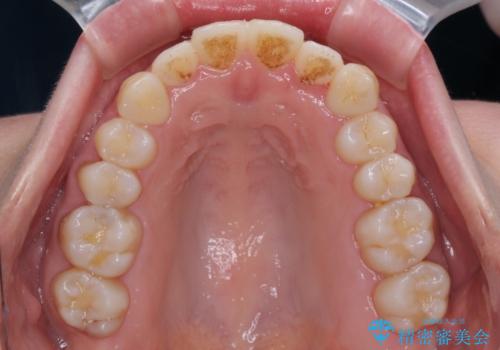

- 受け口傾向でクロスバイトの前歯を治したいとのことで来院された患者様です。

下顎骨が若干左側に変位していたため、右側にアンカースクリューを使用し、積極的に移動させながらインビザラインにて矯正治療を行うこととしました。

インビザラインによる矯正治療は、受け口傾向の治療に非常に適した方法であり、事前にシミュレーションに沿って治療を進めることできます。

今回の治療では骨格的な偏位があったためアンカースクリューを使用し、より確率の高い治療を行うことができました。